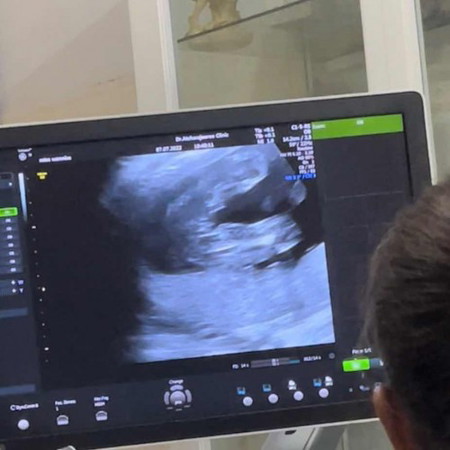

อยากทราบว่า น้องเพศอะไร

แม่ดูไม่ออก ว่าน้องเป็นลูกสาวรึลูกชาย #ท้องแรกคะ #ขอบคุณล่วงหน้านะคะ #คุณแม่ๆช่วยแนะนำหน่อยค่ะ

น่าจะลูกสาวค่ะ เห็นชัดตรงกลาง เหมือนจะเป็นกลีบจิมิ

เหมือนจะเป็น ผู้หญิงค่ะ แต่ก็มีแหลมๆออกมาเหมือน ผช.

แฮมเบอร์เกอร์ไหมแม่ ซาวได้เหมือนกัน ออกแล้วได้ญ.คะ💖